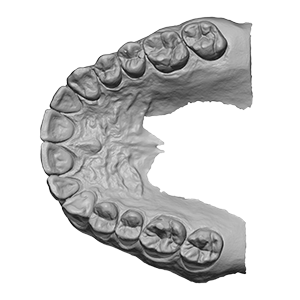

Oberkiefer-Scan

Oberkiefer-Scan

Oberkiefer-Scan

„Viade models by Trios UpperJawScan.stl“